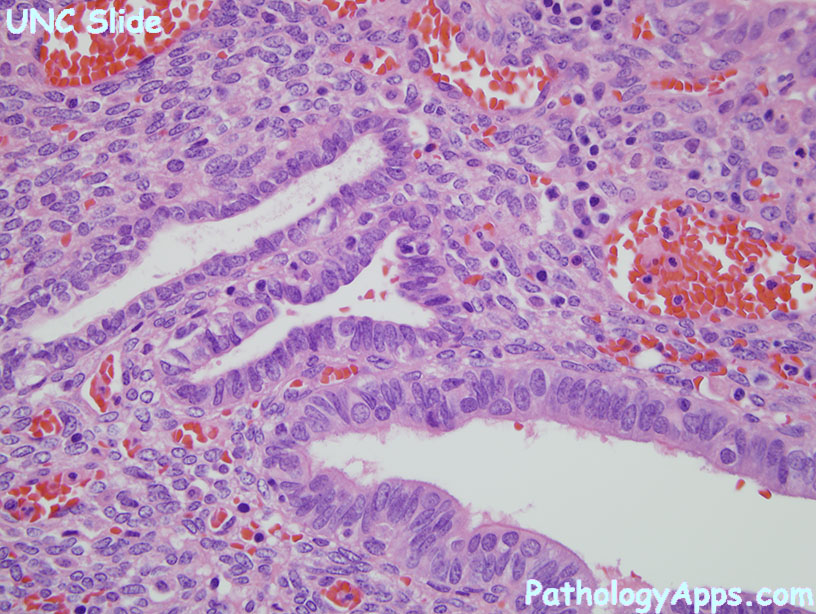

Гистологические изображения фолликулярной кисты яичника